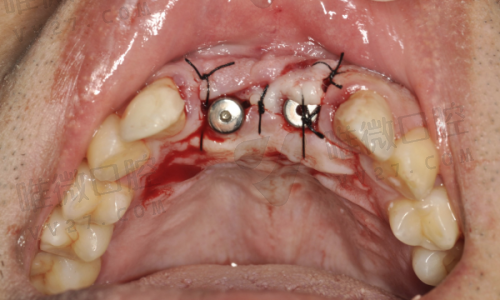

难度较高的情况下,如半口修复、全口重建所用的All-on-4、All-on-6技术,价格则如下:

- 半口(4-6颗种植体支持固定式)价格约:1.5万~3万起

- All-on-4方式半口重建价格:约5万元起

- All-on-6方式半口重建价格:约6万元起

- 全口即刻修复All-on-4方案:约10万元起

- 全口All-on-6:12万元及以上